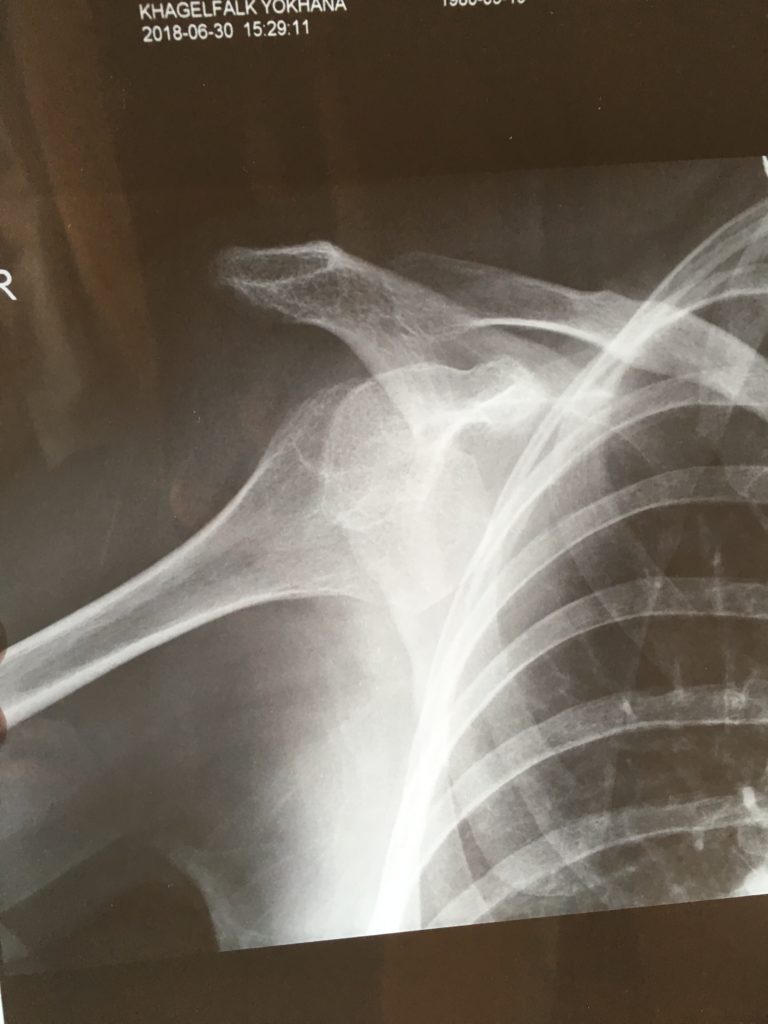

Väl framme fick jag komma in på ett undersökningsrum efter bara några minuter. Det enda som hindrade dem att sätta igång var att de ville ha klart att jag kunde betala för mig. ”Cash or credit card?” När betalningen var säkrad släpptes jag in i undersökningsrummet. Där satt en manlig läkare  som inte rörde sig ur fläcken från sin plats bakom skrivbordet. Tack och lov kunde den här mannen engelska, så jag blev nöjd sv bara vetskapen att han begrep vad jag sa. Och så var det dags för utfrågning igen.  Hur gammal var jag? Vilka sjukdomar hade jag? Hade det hänt förut? … så snart alla frågor besvarats och alla mediciner avhandlats så fick jag komma till ett färdiginställt röntgenrum. Det var bara att ställa sig på plats, och sköterskan knäppte av. Så ut igen och tillbaka till undersökningsrummet. Det hade dykt upp ytterligare en manlig läkare som tydligen var den som skulle fixa armen. Röntgensköterskan kom med bilden och läkarna bestämde att det var dags att göra något åt problemet.

Axel ur led

Riktigt såhär ska det inte se ut

Så fick jag kliva iväg igen, fortfarande med armen på ställningen. Nu hamnade jag i ett rum som såg ut som ett operationsrum. En sköterska med munskydd mötte mig i dörren och läkare nummer två hjälpte mig att lägga mig på en brits. Så lindades spjälkningen bort och jag försökte slappna av -helt utan framgång. Läkaren kom fram och öppnade locket till infarten i armen och sa: Innan du räknat till tio har du somnat. Jag hann inte ens börja  räkna.

Plötsligt väcktes jag och blev inlindad i en mycket avancerad mitella med kardborreband och remmar hit och dit. -Nu får du gå tillbaka och ta en ny röntgenbild, sen ska du få gå hem. Bilden blev avklarad och jag fick skötselanvisningar för armen. Ingen rörelse på några dagar, och får du ont så får du ta extra medicin. Här är ett recept på smärtstillande. De ska tas intramuskulärt. Har du någon som kan hjälpa dig? Hmm, sa jag och tänkte på hur F reagerar på sprutor, det blir nog bäst om jag gör det själv.